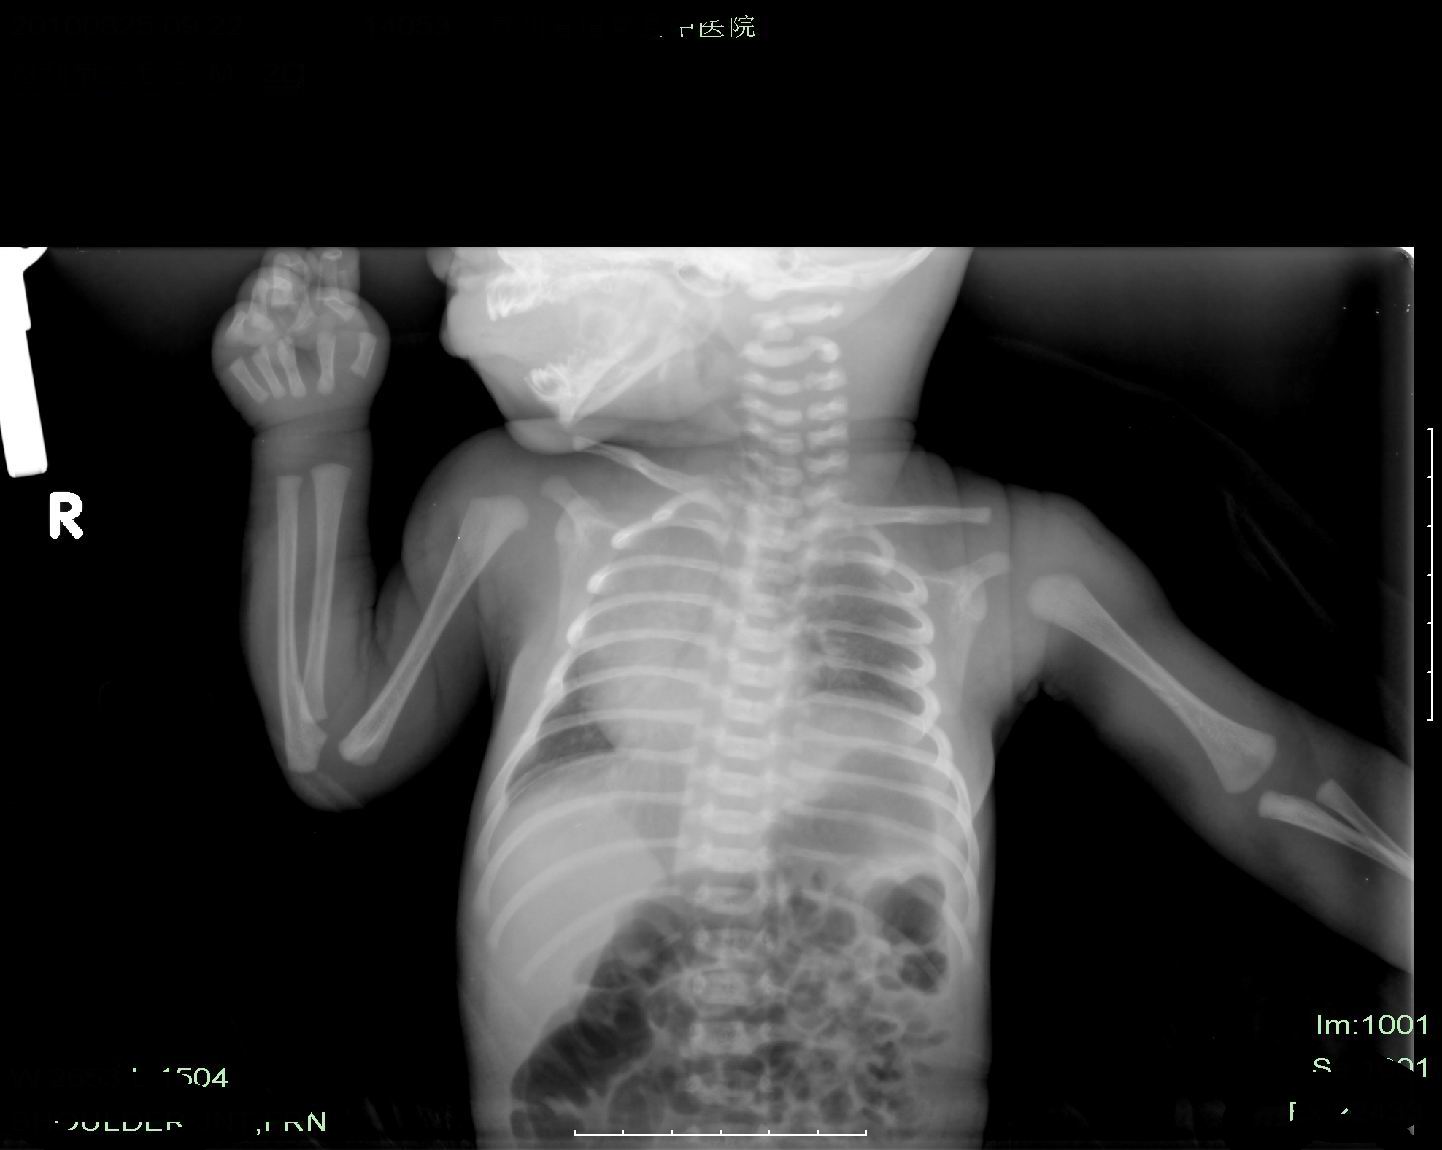

标题: PED3443:新生儿,家中分娩,体征无特殊;左上肢肌力减弱,

体位不正,心肺有否异常不好说,但这个患者中心问题应该在于鉴定有否臂丛神经损伤,拍片只能说左侧上肢骨及锁骨未见明显异常。